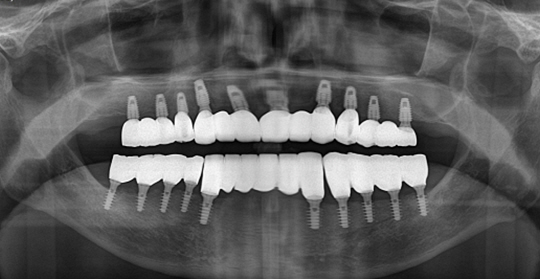

(38세 남 환자)